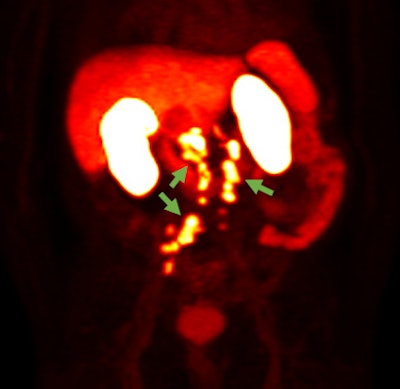

Blue Earth submitted the NDA for the use of F-18 rhPSMA-7.3 in PET imaging of prostate cancer, according to the vendor. The submission was supported by clinical data from one prospective phase I study and two prospective phase III clinical trials, Blue Earth said.